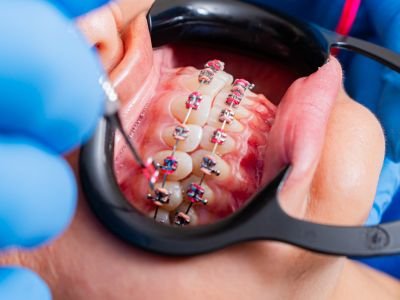

Turismo Dental

Así inicia esta maravillosa experiencia de viajar por tu sonrisa soñada. Nos reunimos de manera virtual💻 para conocernos y aclarar tus dudas, hacemos un plan de tratamiento según tu necesidades, y expectativas.